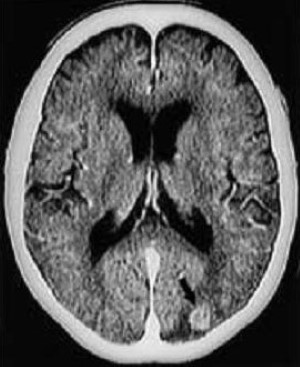

Hình 4 a/b. Glioblastoma? Bệnh nhân nữ 75 tuổi bị rung nhĩ được nhập viện, không có triệu chứng thần kinh. (Chẩn đoán cuối cùng: nhồi máu giai đoạn bán cấp ở vùng phân bố động mạch vân ngoài phải). Các ảnh SE T1-W (460/12) cắt ngang (a) và đứng ngang (b) cho thấy tổn thương ngấm thuốc hình vòng không đều ở phần trước nhân nền phải.

a: Tổn thương liên quan đến cả cánh tay trước của bao trong phải.

b: Tổn thương ngấm thuốc được vạch rõ theo sự phân bố của động mạch vân ngoài trên ảnh cắt đứng ngang. Không điều trị, tổn thương co nhỏ tự phát sau vài tuần (không trình bày hình ảnh theo dõi).